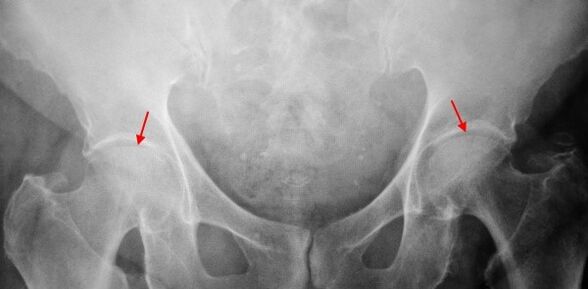

The X -ray patient suffering from first -degree coxarthrosis is determined by mild changes: moderately uneven narrowing of the joint, as well as bone plants around the outer or inner edge of the acetabulum in the absence of changes from the head and neck of the femur.

In X -Remitt images for coxarthrosis of the 2nd degree, a significantly uneven narrowing of the joint gap (more than half of the normal height) is determined.The head of the femur is somewhat displaced up, deformed and increases in size, and its contours become uneven.Bone growths with this degree of coxarthrosis appear not only on the internal but also on the outer edge of the acetabulum and go beyond the cartilage.

In radiographs for 3rd grade coxarthrosis, a sharp narrowing of the joint, a pronounced expansion of the thigh head and multiple bone growth is detected.

The diagnosis of coxarthrosis is based on clinical features and data on additional studies, the main of which is radiography.In many cases, the X -Ribs allow not only the degree of coxarthrosis, but also the cause of its occurrence.For example, increasing the angle of the neck-diaphysis, scenes and acetabulum alignment show dysplasia, and changes in the form of proximal part of the femur are indicated that coxarthrosis is a consequence of the disease of song or youth pinealism.Radios of patients with coxarthrosis may also detect changes showing injuries.